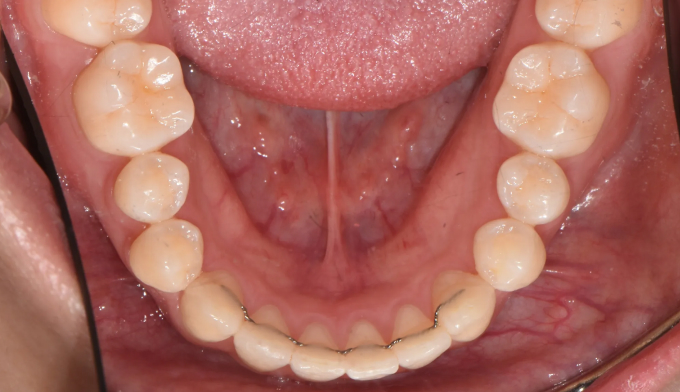

총 치료기간은 15개월 소요되었습니다.

거꾸로 물려있던 앞니를 앞으로 보내면서, 아래치열은 사랑니발치 후 미니스크류를 이용하여 후방이동시켰습니다.